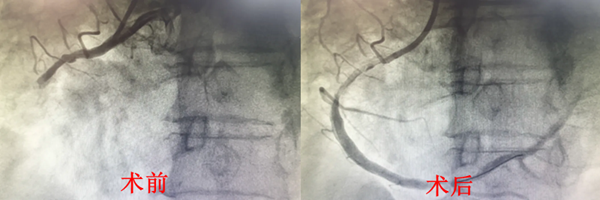

然而紧随其后再现另一难题,造影显示黄奶奶的冠状动脉存在罕见的变异!心脏左前降支开口于右窦,左回旋支缺如,异常粗大的右冠状动脉近段急性完全闭塞,中段严重狭窄。

面对严峻挑战,救心团队最终不负所望,在冠状动脉抽出长达4厘米的血栓,并植入两枚支架。黄奶奶的心律即刻恢复正常,成功闯过鬼门关。进入导管室到导丝通过仅用时19分钟,DtoW 66分钟。